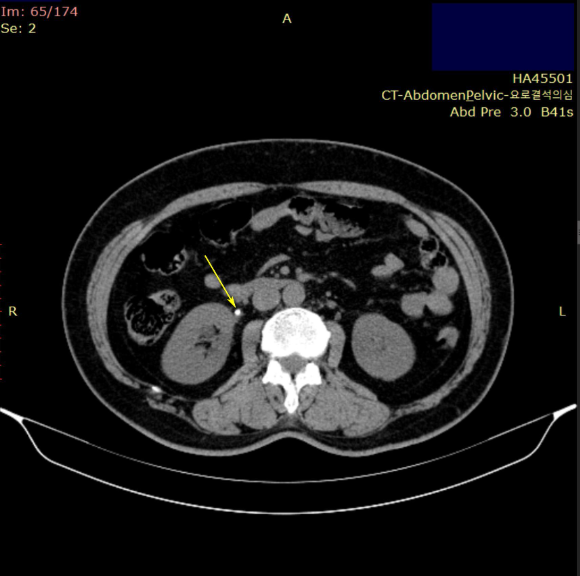

CT검사를 진행하였습니다.

CT검사상

우측 요관 결석과신장 결석이 진단**되어

돌을 깨는 쇄석술을 받으셨고요.